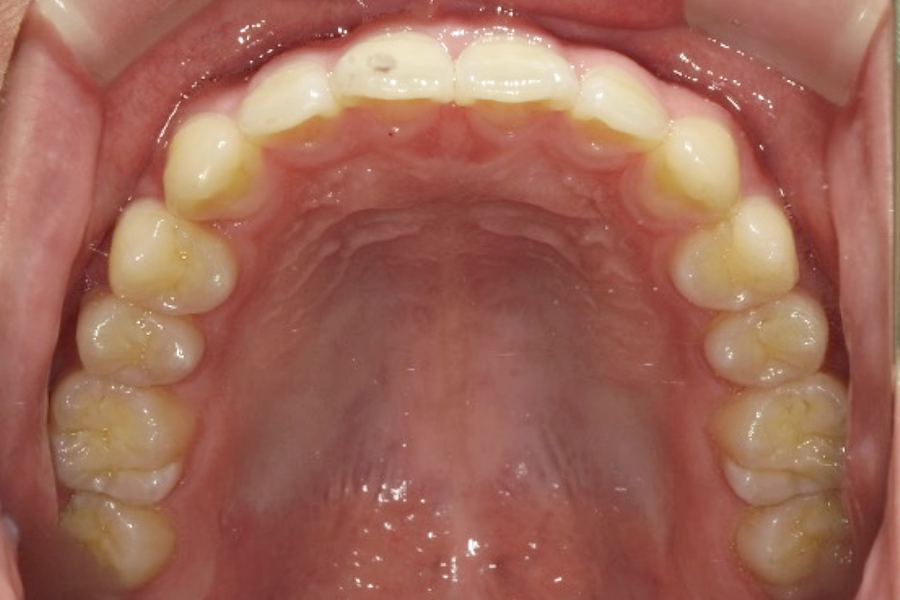

| 主訴 | 前歯のガタガタを治したい |

|---|---|

| 診断名 | 叢生 |

| 年齢 | 21歳 |

| 治療期間 | 3年 |

| 治療費 | 基本料金 ¥880,000 調整料 ¥5,500/月 |

| 治療内容 | 上下顎左右側第一小臼歯抜歯 マルチブラケット装置(表側) |

| 治療のリスク | 装置の見た目、歯ブラシが難しい、疼痛、口内炎、歯肉退縮、歯根吸収 |